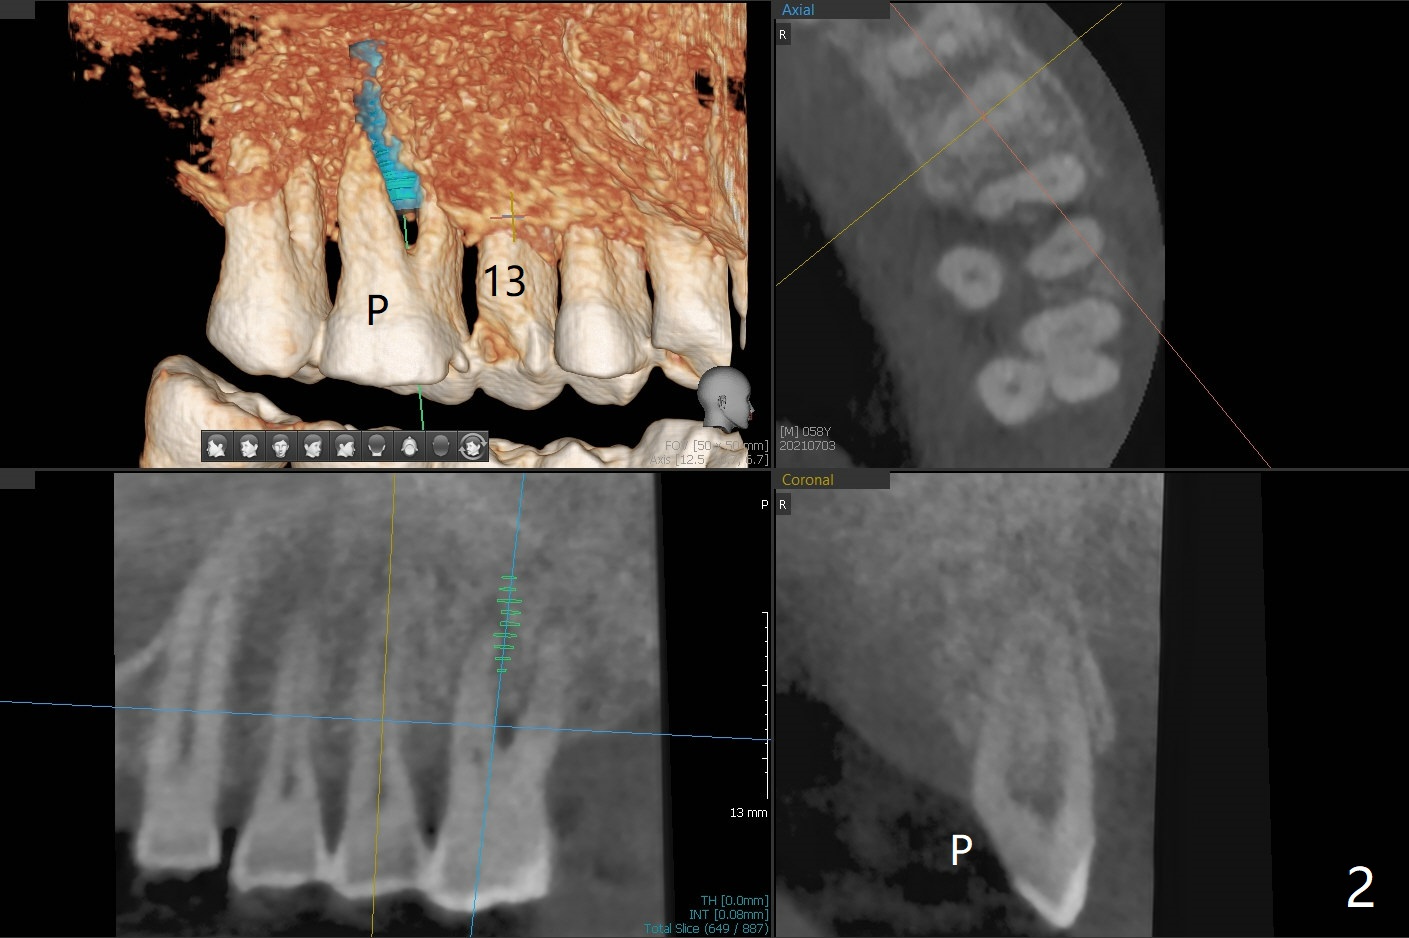

腭侧骨质吸收:颊侧植入

58岁男要求治疗14号牙,吃饭剧痛,CT检查显示腭侧(P)骨质吸收,所以颊侧植入较小植体(图一),13号牙腭侧牙尖折裂(图二),需要牙冠修复。